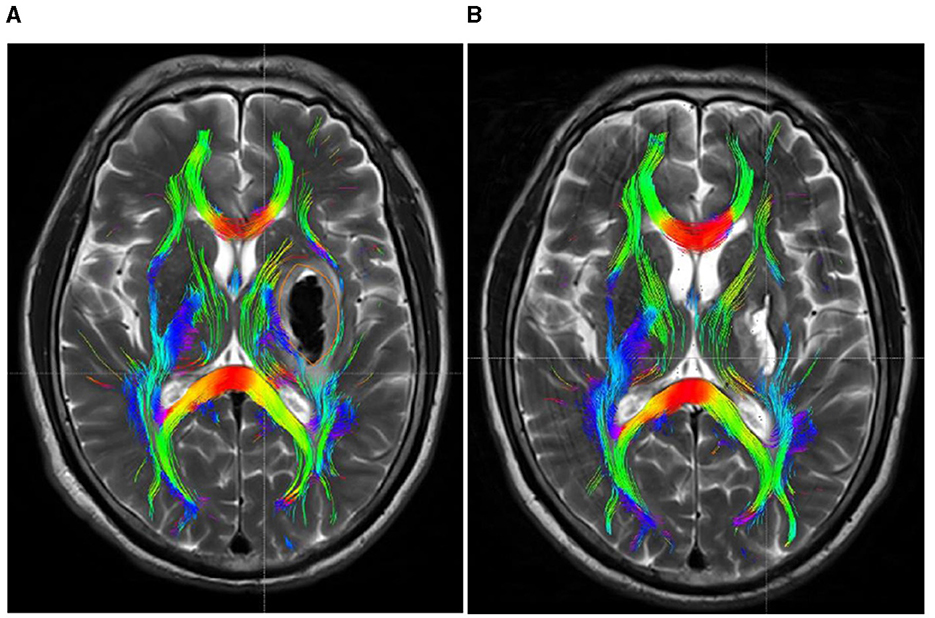

Figure 4

DTI picture of a patient exhibiting a minor basal ganglia hemorrhage, treated with stereotactic intervention within 48 h of admission (A) and 1 month (B). A hematoma is located within the orange marker, resulting in distortion and deformation of the posterior limb of the internal capsule due to compression by the hematoma, which leads to disconnection of a portion of the CST. (B) Upon complete absorption of the hematoma, residual cavities emerge that do not exert pressure on the CST. The CST reverts to its natural anatomical position, with the initial damage primarily evident as additional repair connections.